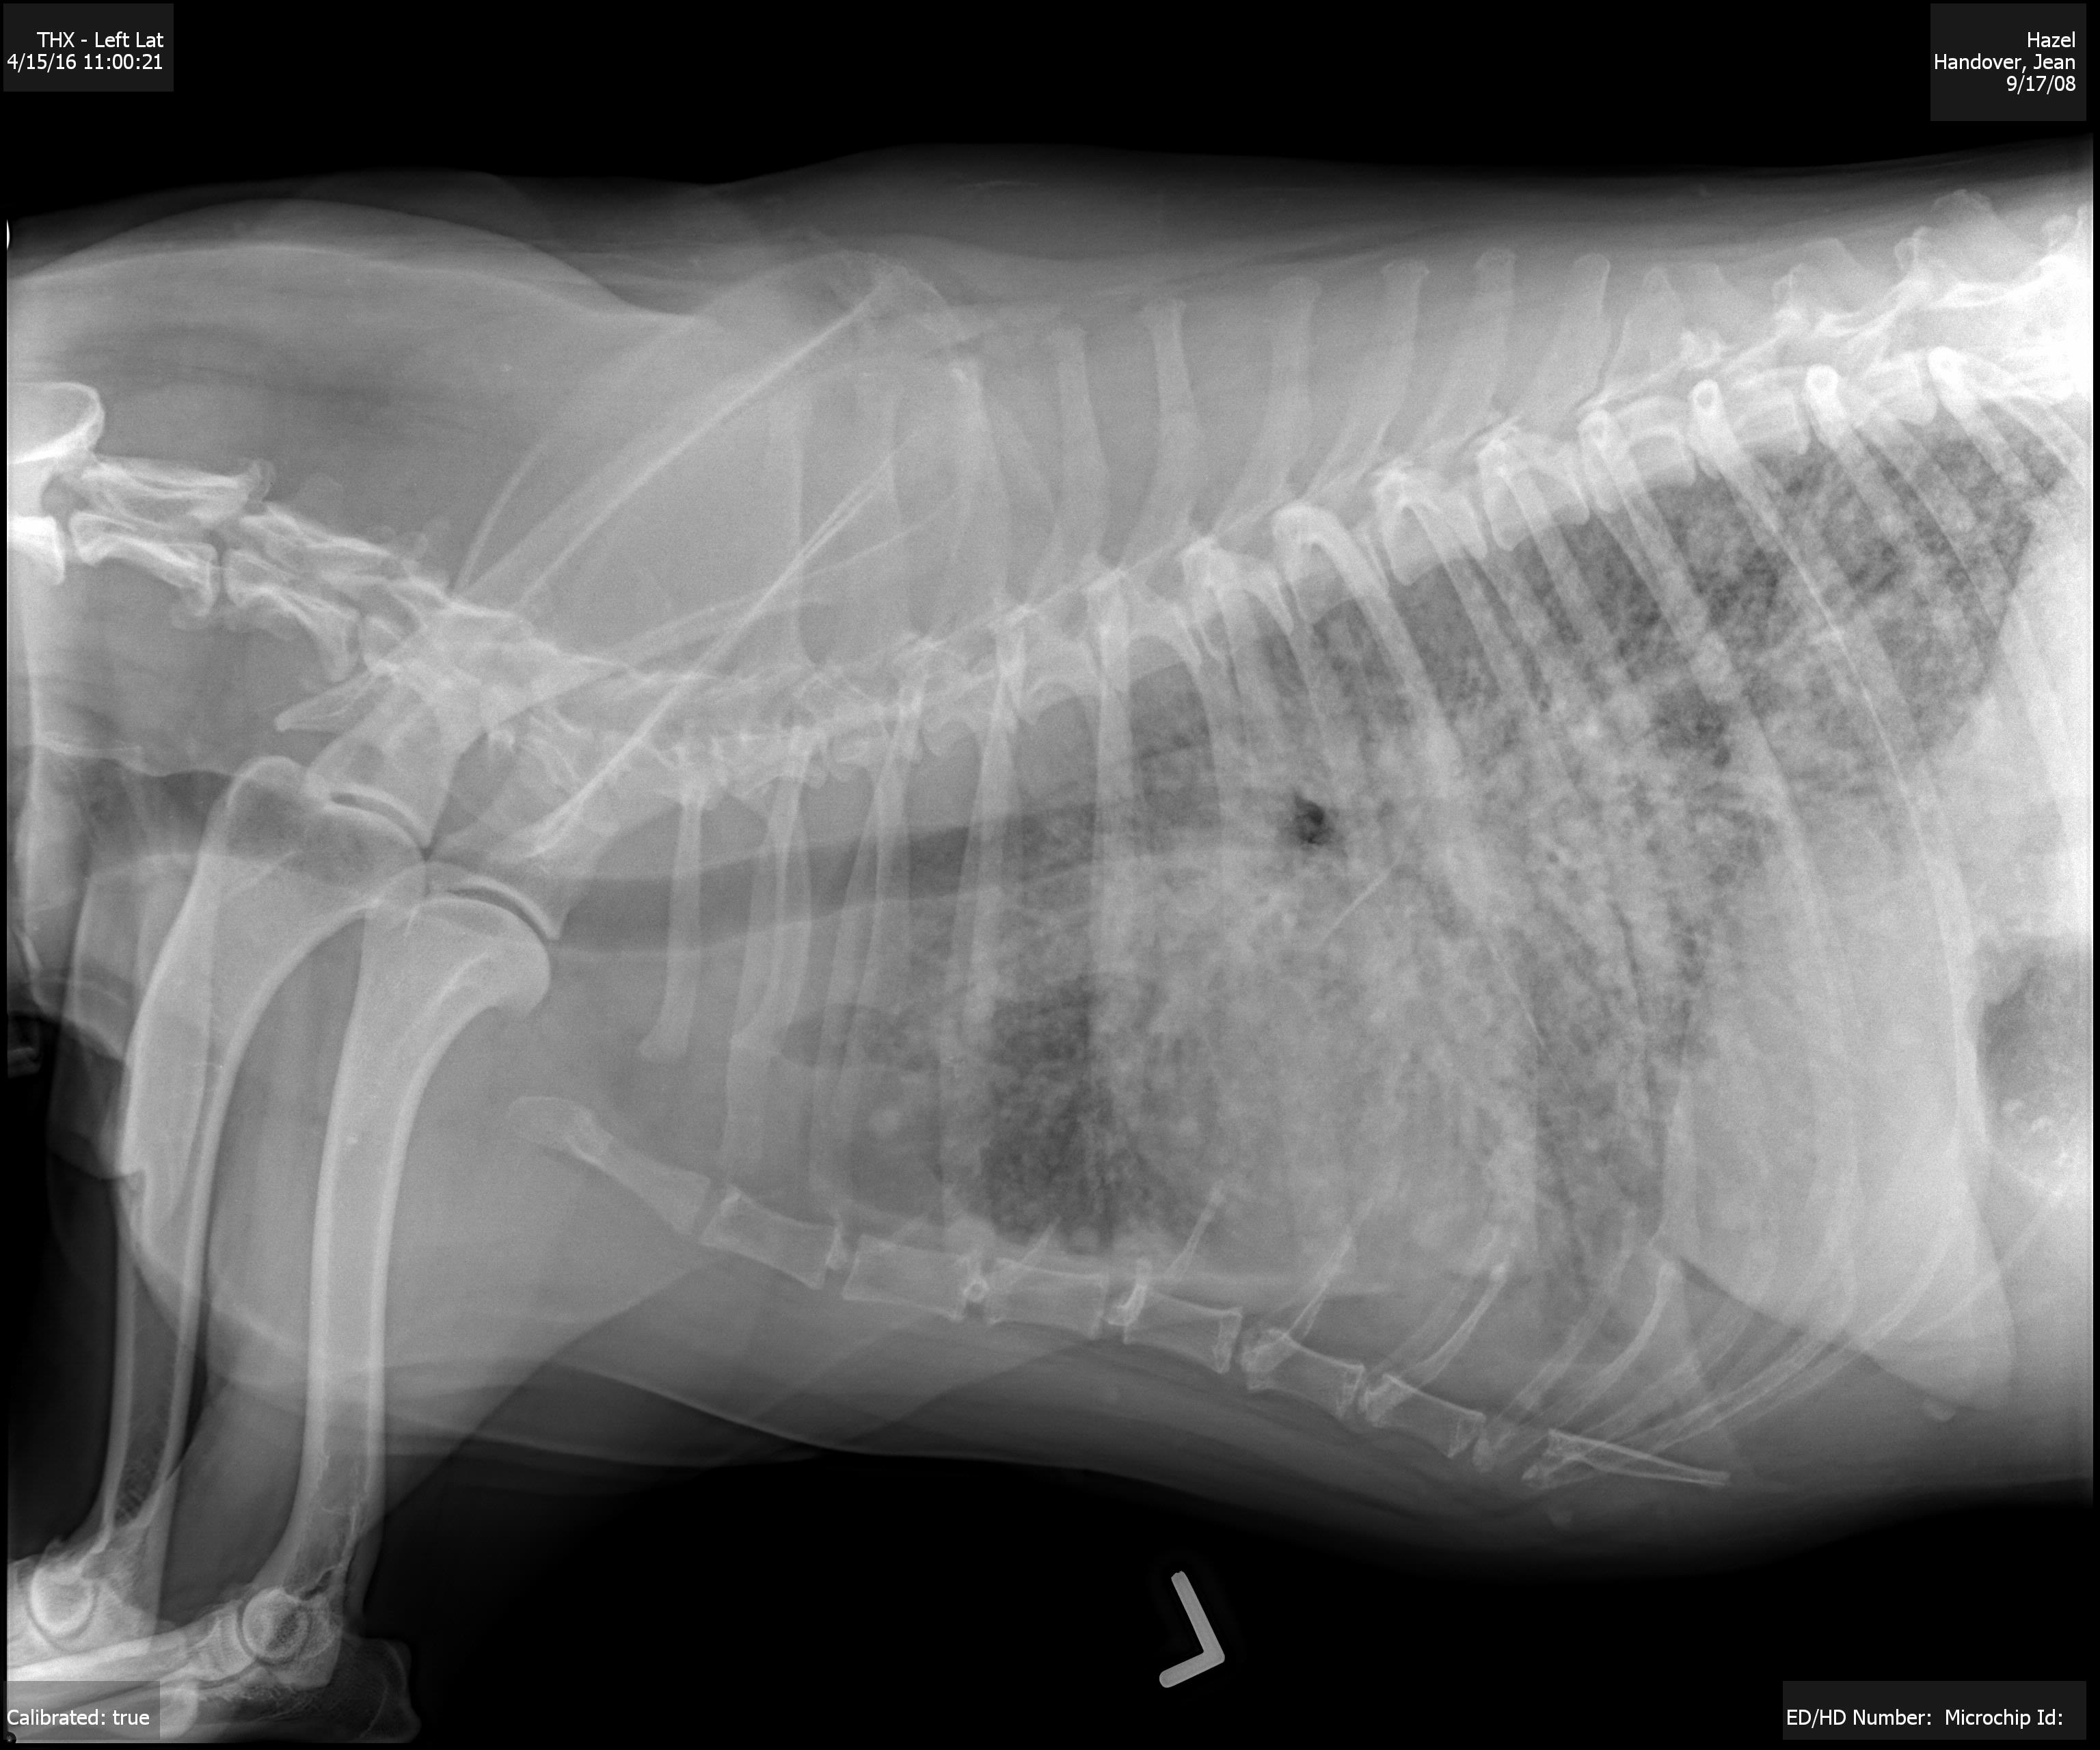

One of the radiographs taken of Hazel.

Then very suddenly last Thursday she started sicking up white, foamy bile and went off her food. Hazel rapidly became lethargic and lacking any vigour. Last Friday we took Hazel to our local Lincoln Road Vet Clinic and she was seen by Dr. Russ Codd, DVM. He took xrays that showed that Hazel’s lungs were far from being as clear as they should be. Potentially, Dr. Codd said that we could be looking at one of three things:

Dr. Codd forwarded the xray pictures to a specialist. Later came the information that the spherules in her lungs, as seen on the xray pictures, were not as would be expected with a cancer diagnosis. Dr. Codd concluded that Hazel was indicating a fungal lung infection. Especially as this is commonly found in hot, drier parts of the USA and Mexico. Hazel was an ex-rescue from Mexico and for a couple of years we lived in Payson, Arizona.